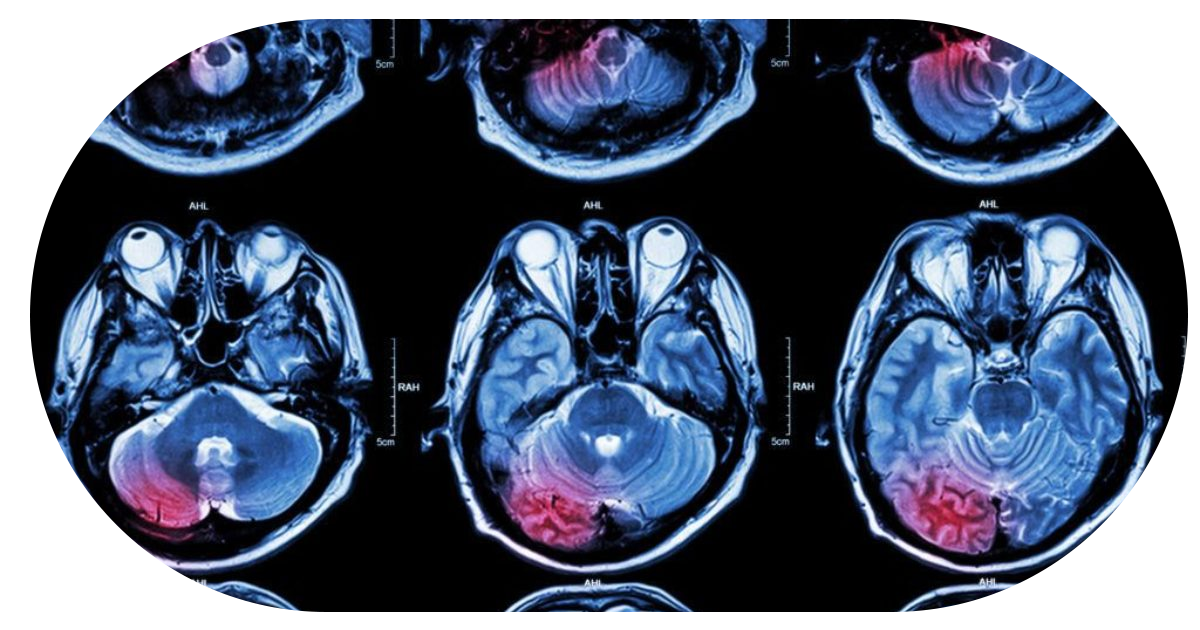

Tumores Cerebrales

Los tumores cerebrales pueden manifestarse con síntomas como dolor de cabeza persistente, náusea, vómito o pérdida de fuerza y sensibilidad.

Una valoración neurológica oportuna es clave para un diagnóstico temprano y tratamiento adecuado.